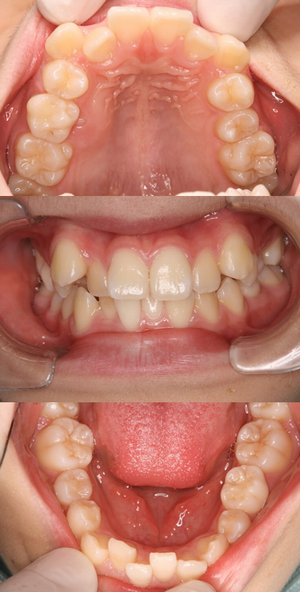

10歳の女の子、上下の前歯がガタガタで八重歯が気になるとのことで矯正相談に来られました。レントゲン撮影をしたところ、下あごの第二小臼歯が1本先天欠損しており、第二乳臼歯(黄色に丸囲い)が残存していることがわかりました。両隣りの永久歯と比較して咬み合わせの位置がずれておらず、根っこもしっかりしています。患者さん自身が非抜歯矯正を希望されているので、今回は乳歯をそのままの状態で抜歯せずに矯正治療を行うことになりました。上下顎ともに叢生量が大きい(ガタガタの度合いが大きい)ので、SH療法にて治療を計画しました。(小学生のレントゲン撮影をすると、10~20人に1人の割合で先天欠損が見つかります。)